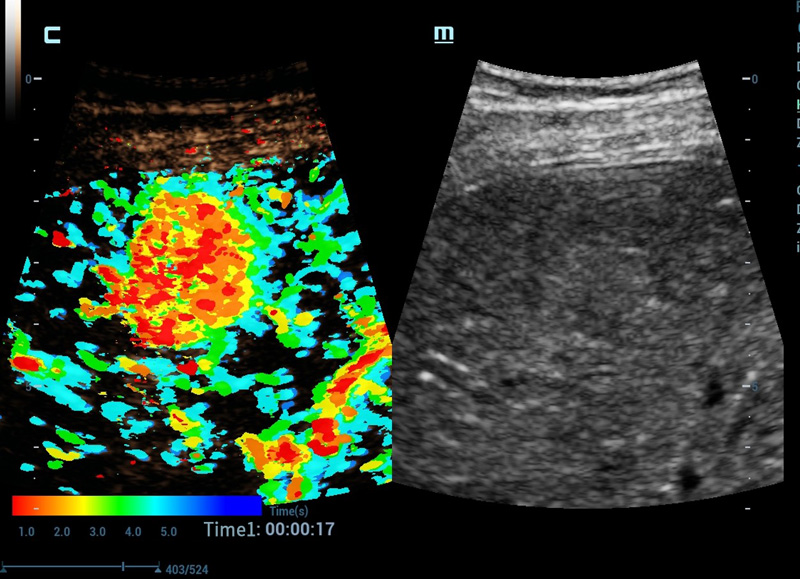

CEUS Chrono parametrische modus

Kleur uw CEUS, maak diagnose makkelijker

Geavanceerde CEUS

Geavanceerde CEUS